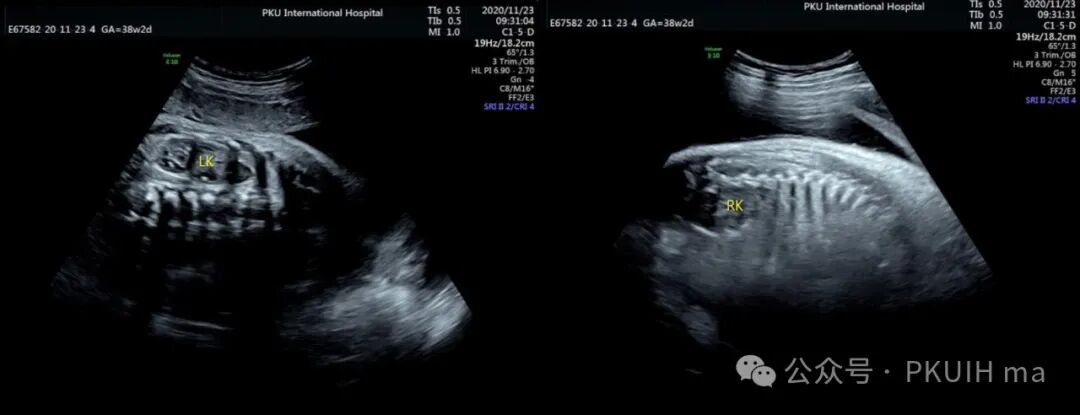

神经母细胞瘤是儿童时期最常见的肿瘤之一,其发病率为1/10,000 -30,000儿童。神经母细胞瘤可在妊娠晚期被诊断出来。产前诊断的肿瘤往往较小,90%涉及肾上腺。囊性和实性区域是典型的,可伴有出血和坏死。囊性病变预后较好。神经母细胞瘤可有微钙化,伴有声影、完整包膜和造成肾脏下移。这些肿瘤可能出现在颈部、胸部或腹部椎旁交感神经节的其他部位。引起气道压迫的宫内病变已有报道。肾上腺肿块伴肝肿大提示神经母细胞瘤的诊断。

上图是一例在孕晚期发现的肾上腺占位,生后病理证实为神经母细胞瘤的患儿,生后及时做了治疗预后非常好,目前宝宝各项指标都很好。

这几年我们在孕晚期发现有3例神经母细胞瘤胎儿,预后都很好。在孕晚期超声中建议常规扫查下胎儿双肾区